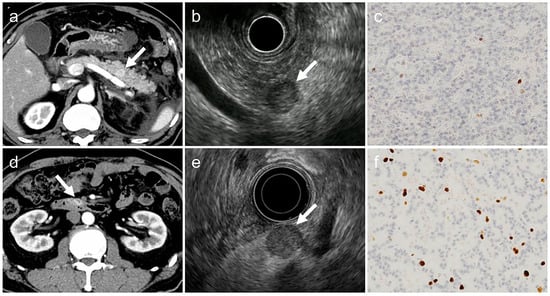

- (a)

- tumor margin contour on EUS (regular or irregular),

- (b)

- internal echogenicity on EUS (homogeneous or heterogeneous),

- (c)

- arterial phase enhancement pattern on contrast-enhanced CT (presence or absence of early enhancement),

- (d)

- presence of calcifications on CT or EUS (identified as hyperechoic structures or high-attenuation areas),

- (e)

- presence of cystic degeneration on CT or EUS (non-enhancing anechoic areas),

- (f)

- main pancreatic duct (MPD) dilation (MPD diameter ≥3 mm on CT or EUS).

- Irregular tumor margins: tumors with spiculated or infiltrative borders in ≥20% of the lesion circumference.

- Heterogeneous echogenicity: tumors with internal echo variability not attributable to cystic changes or calcifications.

- Early enhancement: tumors show greater contrast enhancement than the normal pancreatic parenchyma during the arterial phase.

- Calcifications: hyperechoic areas on EUS correspond to high attenuation on non-contrast CT.

- Cystic degeneration: anechoic regions on EUS without enhancement on any contrast-enhanced CT phase.